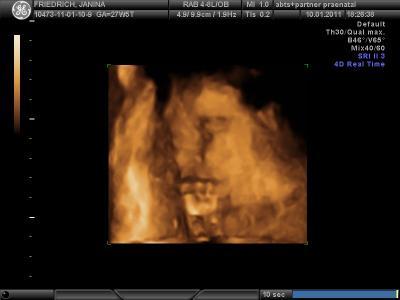

sooo...wie erwartet hat sich melvin nicht so gezeigt... wie wir es gerne hätten. schade, aber man konnte nix machen. Der Arzt hat so an meinem Bauch geruckelt und ich bin selbst nochmal aufgestanden um noch etwas zu hüpfen.... leider hatte er immer wieder seine hände im gesicht oder es war zwischen plazenta und kind kein fruchtwasser. :( Trotzdem hänge ich mal 2 Bilder ran... auf dem einen bild ist echt nicht zu verkennen, dass es ein junge wird... hihii.. ansonsten ist melvin ca. 40 cm und wiegt stolze 1200 gramm...

hihi danke =) war aber dennoch schön ihn zu sehen...zwischendurch hat er gegähnt etc. war schon zuckersüss ihn so anzusehen :) Und ja, er ist wirklich schon ganz groß mein kleiner :) Freu mich nun noch mehr auf den kleinen mann...kann es kaum noch abwarten.. :)

Süß, der kleine Melvin!! Und das 2. Bild ist echt cool!